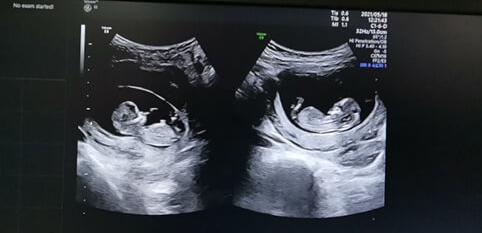

正是因为这些不确定因素的存在,移植两个胚胎后,可能出现多种情况。有可能两个胚胎都成功着床,最终迎来双胞胎的喜悦;也有可能只有一个胚胎成功扎根,发育成一个健康的宝宝;甚至还有可能出现两个胚胎都未能着床的情况,这无疑会给期待新生命的家庭带来巨大的心理落差。